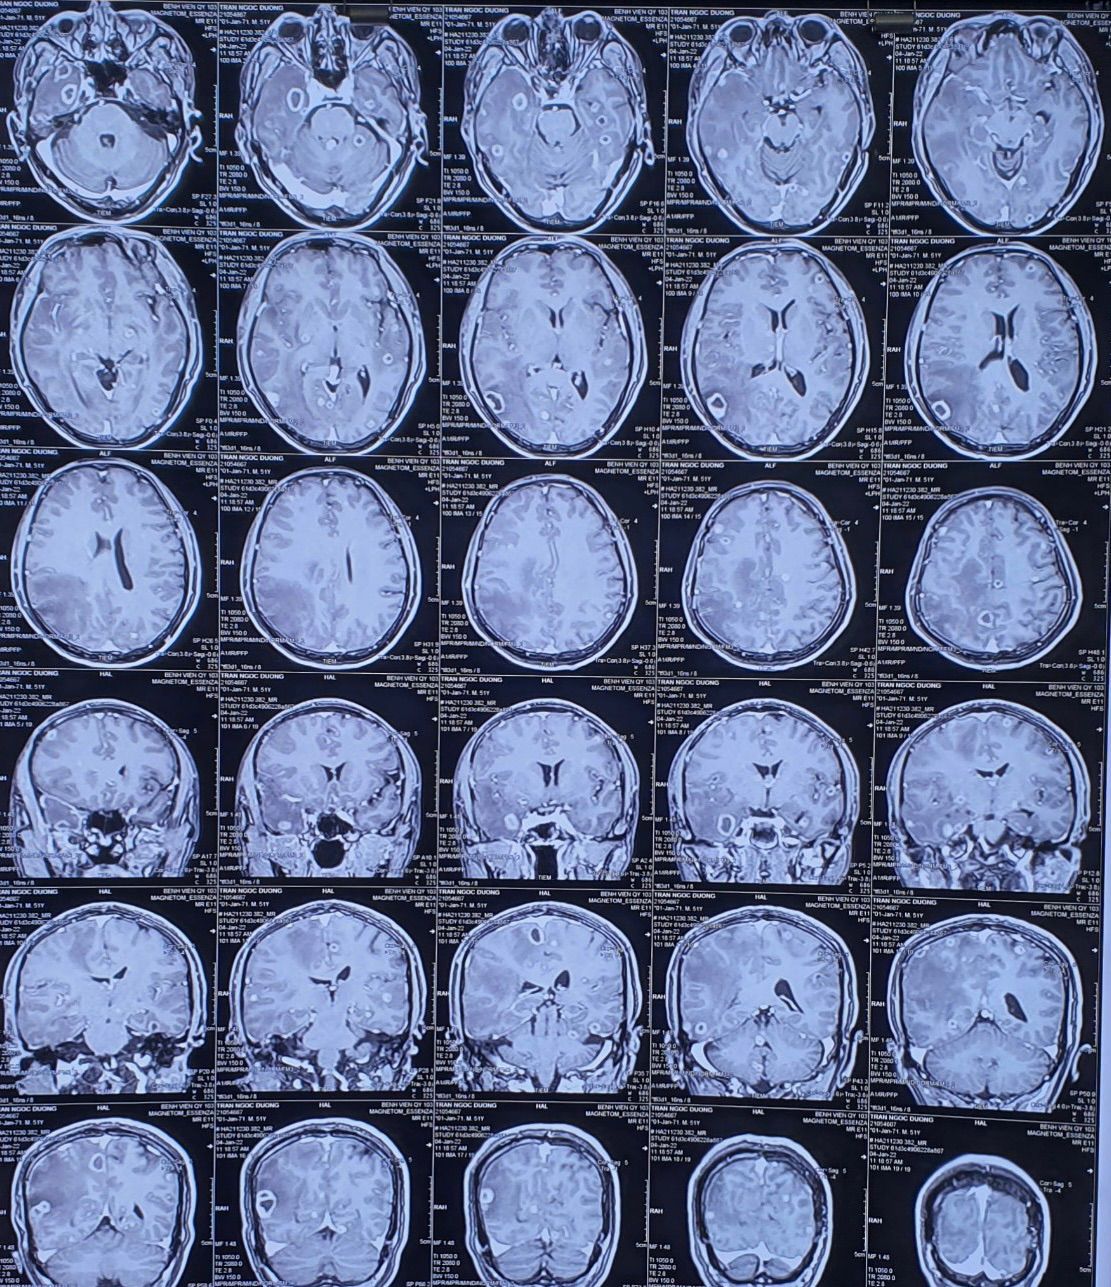

We see multiple ring enhanced lesions in this MRI Which has a long list of differential diagnoses most importantly among them are: -multiple pyogenic abscesses (in context of bacterial endocarditis) -opportunistic parasitic and fungal infections ( in context of immunodeficiency syndrome such as AIDS). Toxoplasmosis, Nocardia abcessess and…. - multiple brain metastases ( lung , breast, GI, GU, melanoma ….) -lymphoma( primary or secondary) - less commonly multiple glial tumors.